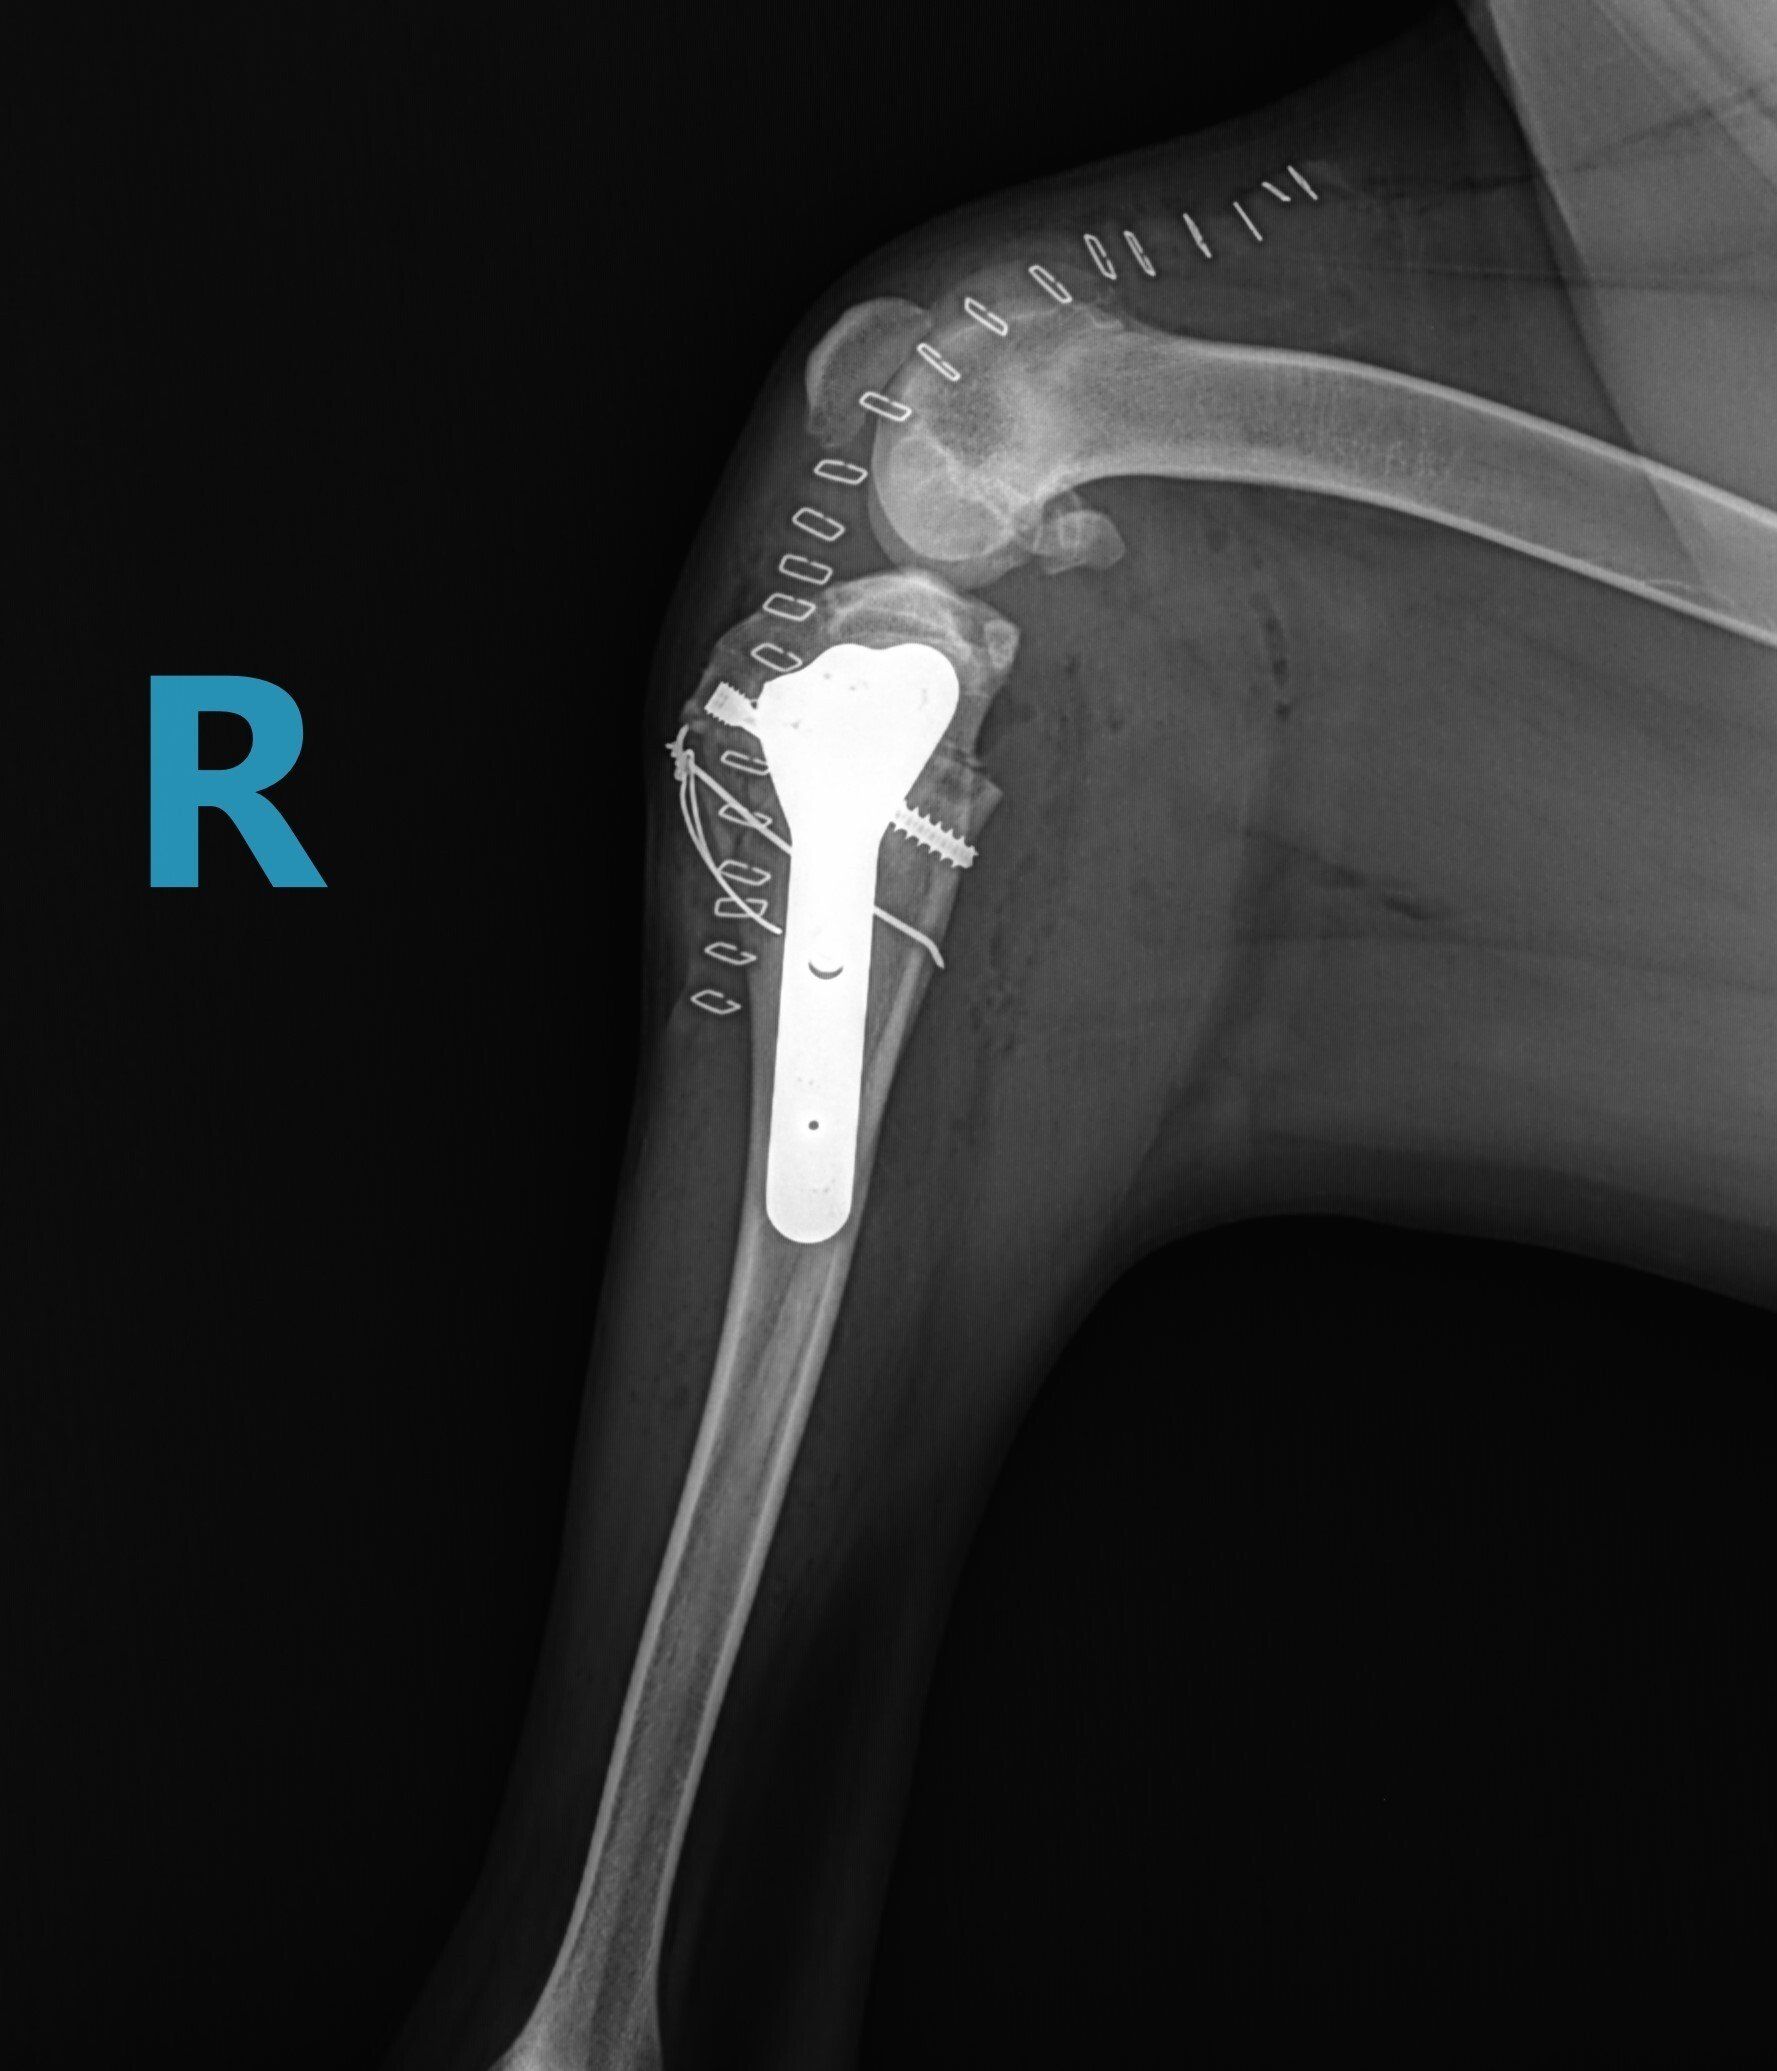

ButtonTPLO Surgery

Tibial Plateau Leveling Osteotomy (TPLO) is a procedure that modifies the geometry of the knee joint in dogs to allow a return to function after a CCL rupture. This is accomplished by making a semi-circular cut to the top portion of the tibia (shin bone). This top portion of the bone is then rotated to decrease the tibial plateau angle. This decrease in angle decreases or eliminates the instability and pain associated with having a ruptured CCL. Once the cut and rotation are made, a specialized plate and screws are placed to allow healing of the bone, which can take up to 12 weeks. The majority of the time this plate will stay in place for the remainder of your pet’s life. There are rare occasions in which the plate needs to be removed (infection, cold sensitivity, etc.). Once the bone is healed, the plate is no longer needed and can be removed with no adverse effects.

Below are x-rays of just a few orthopedic surgeries before and after that Dr. Gose has performed.